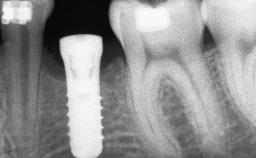

A 47-year-old woman who had suffered from aggressive periodontitis requiring a number of periodontal interventions over more than 10 years was referred by her general dental practitioner and periodontologist for bone augmentation and implant therapy. Her failing dentition had already been scheduled for extraction. The patient expressed a desire for implant-supported fixed restorations and esthetic improvement of her lower face. She had agreed to consult with a maxillofacial surgeon after the referring dentist had suggested bone augmentation. An initial examination by the maxillofacial surgeon revealed mobility of all residual teeth in a patient who was very unhappy with the function of her removable partial dentures. Due to periodontally migrated flaring teeth and loss of occlusal support, the vertical dimension of occlusion was dramatically reduced. The patient was displeased with her lower face because of deepened nasolabial, commissural, and supramental folds.

Bone Augmentation Horizontal|Sinus Floor Elevation|Staged|Vertical

Augmentation Materials Autogenous chips|Autogenous block(s)|Xenogenous|Membrane

Bone Volume Deficient vertically or deficient vertically AND horizontally